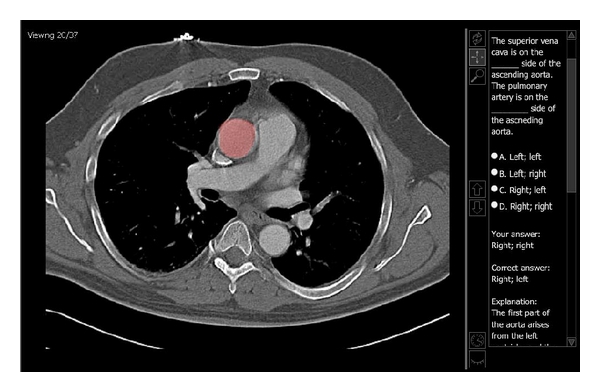

Current generations of graduate students have been immersed in technology from their early school years and have high expectations regarding digital resources. To better meet the expectations of Gross Anatomy students at our institution, electronic radiology teaching files for first-year coursework were organized into a web site. The web site was custom designed to provide material that directly correlated to the Gross Anatomy dissection and lectures. Quick links provided sets of images grouped by anatomic location. Additionally, Lab and Study Companions provided specific material for the students to review prior to and after lectures and gross dissections. Student opinions of this education resource were compared to student opinions of the prior year's digital teaching files. The new content was ranked as more user friendly (3.1 points versus 2.3 points) and more useful for learning anatomy (3.3 points versus 2.6 points). Many students reported that using the web portal was critical in helping them to better understand relationships of anatomical structures. These findings suggest that a well-organized web portal can provide a user-friendly, valuable educational resource for medical students who are studying Gross Anatomy.